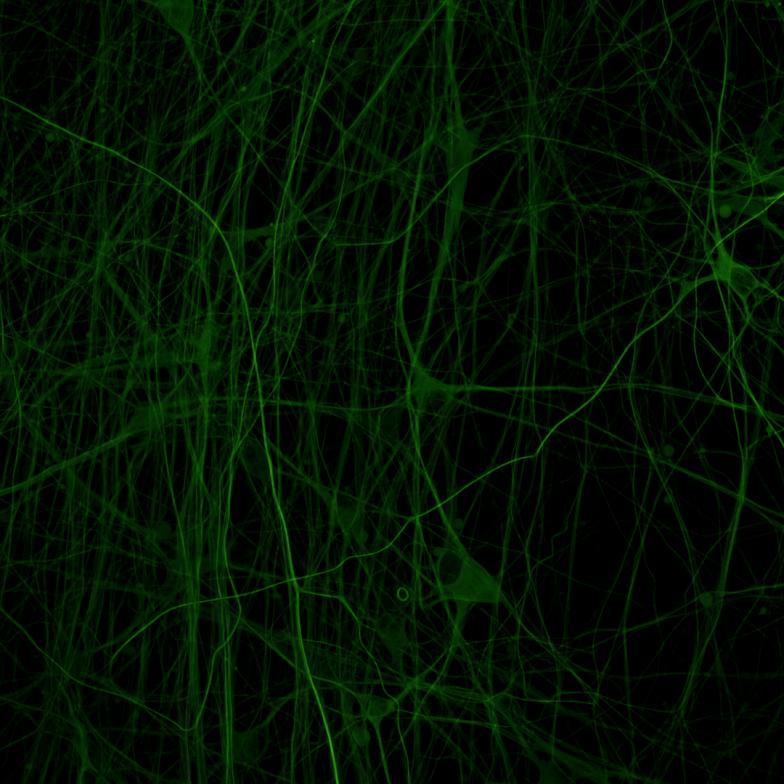

• Wildtype neurons were transduced with a lentivirus to express a full-length 4R tau isoform with a familial frontotemporal dementia P301L mutation labelled with EGFP

• Neurons were then exposed to recombinant tau preformed fibrils (PFFs) and imaged

• Increasing over time, PFF exposure induced areas of bright EGFP-positive aggregates of full-length tau, and aggregation of the K18 fragment FRET pair as seen by positive normalised FRET (NFRET) signal

• K18 PFFs with P301L mutation induced aggregation more readily than full length 2N4R PFFs in both systems